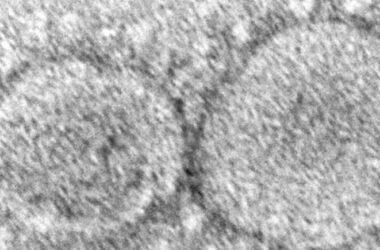

Un total de 57 países han detectado ya casos de la nueva variante ómicron del coronavirus, aunque muchos de ellos sin síntomas, o leves, destaca la Organización Mundial de la Salud (OMS) en un informe donde alerta sobre la alta posibilidad de reinfección que parece tener la nueva cepa.

La OMS advierte sin embargo que aunque la variante ómicron pueda causar menos casos graves que la delta (predominante en la actualidad) podría aumentar las hospitalizaciones y las muertes si, como se teme, es más contagiosa y causa más infecciones en general.